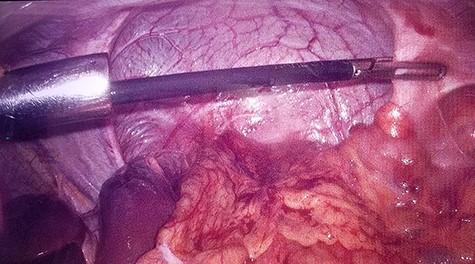

Intraoperative laparoscopic view of left diaphragmatic eventration.

A 19-year-old male with no known co-morbidities presented to the emergency department with 2-day history of severe upper abdominal pain and vomiting. He complained of similar episodes over the past 2 years, which used to get relieved spontaneously. On examination, the patient was tachycardic (110 bpm) with normal blood pressure and normothermic. The upper abdomen was asymmetrically distended, non-tender with a tympanic note. The laboratory investigations were within normal limits. Chest X-ray revealed markedly elevated (>4 cm) left hemi-diaphragm, huge gastric shadow with an air-fluid level and shift of mediastinum toward the right side (Fig. 1). Acute gastric volvulus was suspected based on the above finding, which was confirmed with contrast CT. Patient underwent initial laparoscopic evaluation, which was converted to open procedure. Intraoperatively, there was an organo-axial volvulus without any vascular compromise secondary to diaphragmatic eventration. It was de-rotated, decompressed and anterior abdominal wall suture gastropexy done. The freely mobile stomach was further reinforced with sham (trans-seromuscular) gastrojejunostomy. Left diaphragmatic eventration was plicated with polypropylene suture number 1 (Fig. 2) for which it required open conversion. Postoperative period was uneventful and discharged on Day 6. At 16-month follow-up, patient is doing absolutely fine.